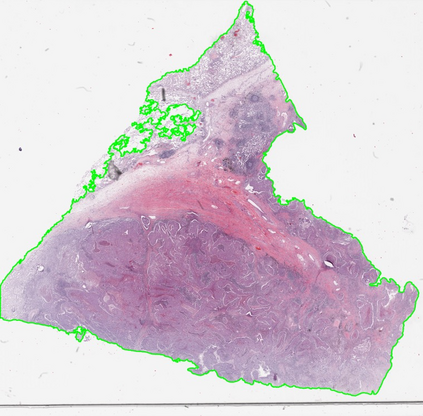

Multiple instance learning (MIL) is a powerful approach to classify whole slide images (WSIs) for diagnostic pathology. A fundamental challenge of MIL on WSI classification is to discover the \textit{critical instances} that trigger the bag label. However, previous methods are primarily designed under the independent and identical distribution hypothesis (\textit{i.i.d}), ignoring either the correlations between instances or heterogeneity of tumours. In this paper, we propose a novel multiplex-detection-based multiple instance learning (MDMIL) to tackle the issues above. Specifically, MDMIL is constructed by the internal query generation module (IQGM) and the multiplex detection module (MDM) and assisted by the memory-based contrastive loss during training. Firstly, IQGM gives the probability of instances and generates the internal query (IQ) for the subsequent MDM by aggregating highly reliable features after the distribution analysis. Secondly, the multiplex-detection cross-attention (MDCA) and multi-head self-attention (MHSA) in MDM cooperate to generate the final representations for the WSI. In this process, the IQ and trainable variational query (VQ) successfully build up the connections between instances and significantly improve the model's robustness toward heterogeneous tumours. At last, to further enforce constraints in the feature space and stabilize the training process, we adopt a memory-based contrastive loss, which is practicable for WSI classification even with a single sample as input in each iteration. We conduct experiments on three computational pathology datasets, e.g., CAMELYON16, TCGA-NSCLC, and TCGA-RCC datasets. The superior accuracy and AUC demonstrate the superiority of our proposed MDMIL over other state-of-the-art methods.

翻译:多重实例学习 (MIL) 是用于诊断病理的全幻灯片图像分类的有力方法。 MIL 在 WSI 分类上的一项基本挑战是发现触发包标签的\ textit{ 关键事件} 。 但是, 先前的方法主要是在独立和相同的分布假设(\ textit{i. id})下设计的, 忽略肿瘤的发生或异质之间的相互关系。 在本文件中, 我们提议采用新型的多克斯检测性多重实例学习( MDMIL) 来解决上述问题。 具体地说, MDMIL 是由内部查询生成模块( IQGM) 和多x检测模块( MDMMIL ) 构建的, 并借助基于记忆的对比性分布式假设(\ textitilitalital) 。 IQGMGM提供实例的概率, 在分布分析后, 集合非常可靠的特性。 第二, 多克斯检测性跨位(MDC) 和多头项自我保存(MHSA) 与MDD(MDA) 合作, 建立内部生成精度的精度精确度(IMDL) 数据, 以生成的精度分析过程, 并测试中, 运行中, 运行中, 运行中, 运行中, 运行中 运行中 运行中 运行中 运行中 运行中 和 运行中 运行中 运行中 运行中 运行中 运行中 运行中 运行中 。